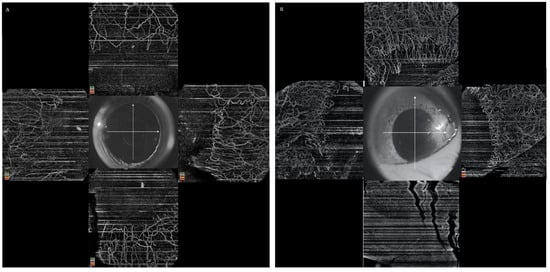

6.1. Role of AS-OCTA

- Ang, M.; Foo, V.; Ke, M.; Tan, B.; Tong, L.; Schmetterer, L.; Mehta, J.S. Role of Anterior Segment Optical Coherence Tomography Angiography in Assessing Limbal Vasculature in Acute Chemical Injury of the Eye. Br. J. Ophthalmol. 2021. [Google Scholar] [CrossRef] [PubMed]

| Ang et al., (2021) [35] | Humans (10) | (i) AngioVue (ii) Plex Elite | 3 | (i) Good agreement between the two devices for the measurement of VD. (ii) OCTA is more reliable than clinical examination for the assessment of limbal ischemia. (iii) Area of ischemia may predict the future development of LSCD. |